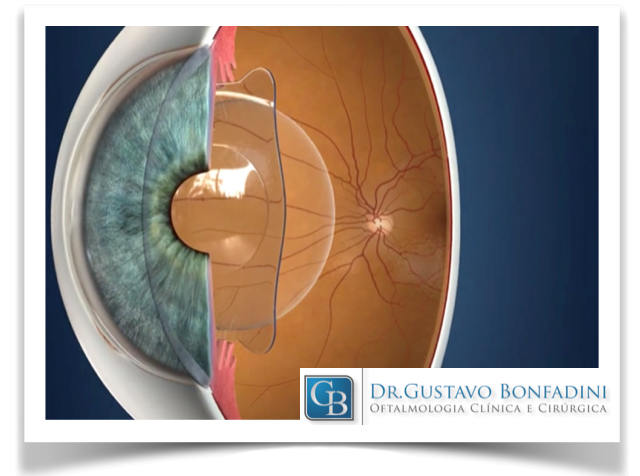

3) Implante de Lente Intraocular (LIO) Fácica no Tratamento do Ceratocone

As lentes intraoculares fácicas de câmara posterior são uma excelente alternativa de correção da visão de pacientes que não podem se beneficiar da cirurgia de implama laser. Elas são indicadas para pacientes que apresentem graus elevados de Miopia, Hipermetropia e Astigmastismo, ou Córneas muito curvas ou finas e em pacientes com Ceratocone – situações onde a cirurgia a laser não são recomendadas. Nesta modalidade de cirurgia, as lentes são implantadas e fixadas à íris (ex: lente de Artisan), na frente da íris (ex: lente Vivarte), ou atrás da íris (ex: lente ICL).

A Lente Artisan – feita de polimetilmetacrilato (PMMA), material inerte empregado para implantes em cirurgias intraoculares – é a lente ocular fácica mais comumente usada no mundo, com um longo histórico de sucesso. Essa lente pode ser usada para corrigir uma alta Miopia (de -5,0 D a -20,0 D) ou corrigir uma alta Hipermetropia (de +5,0 D a +10,0 D). A Lente Artisan tórica pode ser utilizada em graus elevados de astigmatismo, que necessitam de correção.

Vantagens das Lentes Artisan:

– A cirurgia pode ser realizada em paciente com córnea fina e córnea irregular;

– São potencialmente reversíveis;

– Permitem recuperação visual rápida;

– Preservam a acomodação (capacidade de enxergar para longe e perto) em pacientes jovens;

– Boa qualidade de correção da visão;

– Boa precisão de correção da visão.

Os riscos potenciais da cirurgia de implante de Lentes Fácicas, como em qualquer cirurgia intraocular, incluem a possibilidade de infecção e por essa razão é tratado um olho de cada vez, com um intervalo mínimo de 4 semanas entre os tratamentos. Há também raros casos descritos de possibilidade de dano à estrutura interna do olho, o que poderia levar ao Glaucoma, inflamação da íris (uveíte), complicações da retina, Descompensação da córnea ou a formação de uma Catarata precoce. Nesses casos, a Lente Artisan deverá ser removida.

Por essas razões, aconselhamos aos pacientes que cumpram o compromisso de revisões pós-operatórias em longo prazo.